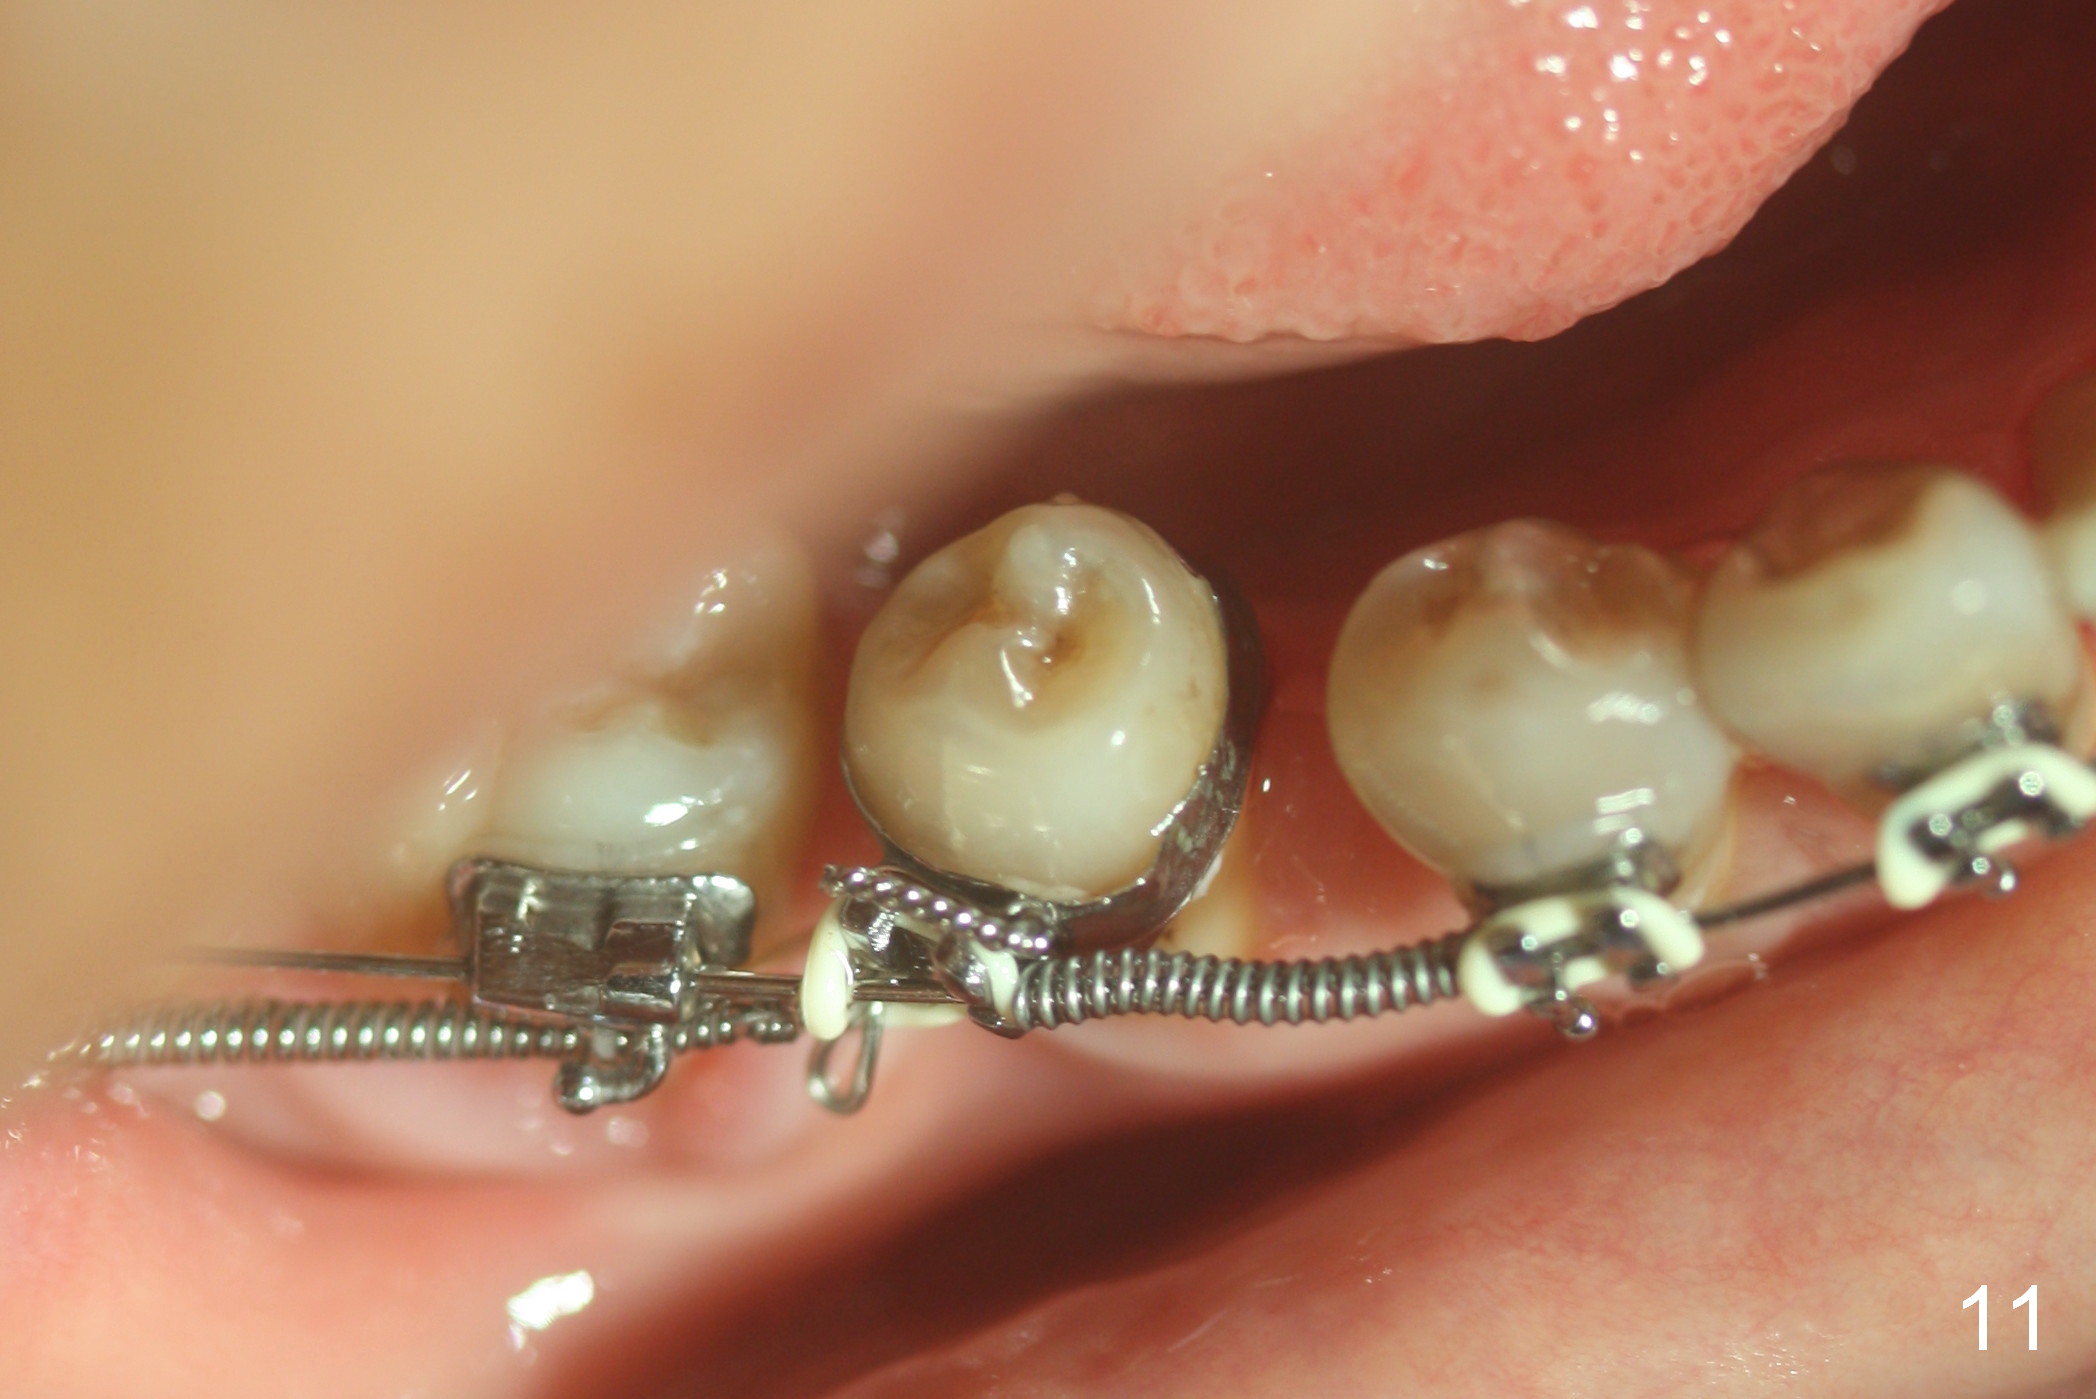

A 47-year-old lady has lost the lower right 1st molar for long time; with reduction of the buccolingual width (Fig.1) and mesiodistal width (Fig.2,3). With regional orthodontic appliance (Fig.4) for 3 months, the tooth #29 has started being distalized (Fig.5). One month and a half later, the tooth #26 starts to shift labially. Power chains and then closed coil spring are placed between #29 and 32. #29 distalization is slow (Fig.7) with closure of the diastema between #31 and 32 (Fig.8, as compared to Fig.1,3). Seven months post banding, a 10 mm miniimplant is placed distobuccal to the tooth #32 (Fig.6); the same 12-mm closed spring is stretched distal by ~ 6 mm (Fig.8 between arrowheads). Two months later, #29 is more distalized (Fig.9 tilted) with bone deposit mesially (*) and coronally (^). A .018' stainless steel wire is installed with an open coil spring placed between #28 and 29 (Fig.10 (^),11). Note #29 rotation (Fig.11). To solve the tilting, a power hook (Fig.12 black) will be clamped to a .016x.016 wire (red), while the closed spring is lowered and attached to the power hook (Fig.12 white). Take photos after removing the existing wire occlusally to show the alveolar width change. When the wire is placed, make sure that the distal wings of #29 bracket is fully engaged to reduce the tooth rotation. Make occlusal adjustment on #31 and 32 to reduce anterior open bite.